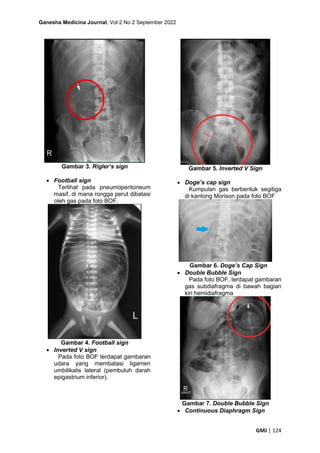

• Rigler’s sign

Udara yang membatasi kedua sisi

dinding usus pada foto BOF.

Gambar 3. Rigler’s sign

• Football sign

Terlihat pada pneumoperitoneum

masif, di mana rongga perut dibatasi

oleh gas pada foto BOF.

Gambar 4. Football sign

• Inverted V sign

Pada foto BOF terdapat gambaran

udara yang membatasi ligamen

umbilikalis lateral (pembuluh darah

epigastrium inferior).

Gambar 5. Inverted V Sign

• Doge’s cap sign

Kumpulan gas berbentuk segitiga

di kantong Morison pada foto BOF

Gambar 6. Doge’s Cap Sign

• Double Bubble Sign

Pada foto BOF, terdapat gambaran

gas subdiafragma di bawah bagian

kiri hemidiafragma

Gambar 7. Double Bubble Sign

• Continuous Diaphragm Sign